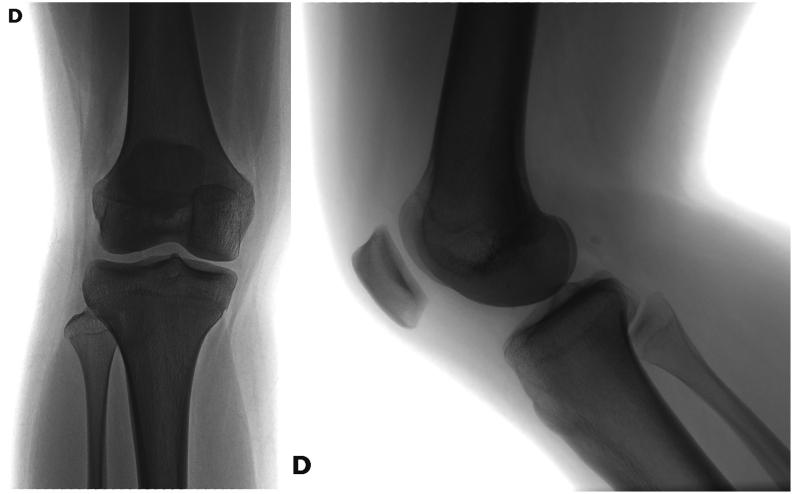

The physis of the distal femur contributes to 70% of femoral growth and 37% of the total limb growth; therefore, physeal injury can lead to important alterations of axes and length. Distal metaphyseal corner-type fracture prior to walking is classically associated with child abuse. In children aged >10 years, sports-related fractures and car accidents are significant contributors. Imaging includes a two-plane radiographic study of the knee. It is recommended to obtain radiographs that include the entire femur to rule out concomitant injuries. In cases of high suspicion of distal metaphyseal fractures and no radiographic evidence, CT or MRI can show the existence of hidden fractures. Fractures with physeal involvement are conventionally classified according to the Salter-Harris classification, but the Peterson classification is also recommended as it includes special subgroups. Conservative and surgical management are valid alternatives for the treatment of these fractures. Choosing between both alternatives depends on factors related to the fracture type. As there is a high risk of permanent physeal damage, long-term follow-up is essential until skeletal maturity is complete.

股骨远端的生长板对股骨生长的贡献率为70%,对整个肢体生长的贡献率为37%;因此,生长板损伤可导致轴线和长度的重要改变。行走前的远端干骺端角型骨折通常与虐待儿童有关。在10岁以上的儿童中,与运动相关的骨折和车祸是重要原因。影像学检查包括膝关节的双平面X线检查。建议获取包括整个股骨的X线片以排除合并损伤。在高度怀疑远端干骺端骨折但无X线证据的情况下,CT或MRI可显示隐匿性骨折的存在。涉及生长板的骨折传统上根据Salter-Harris分类法进行分类,但也推荐使用Peterson分类法,因为它包括特殊的亚组。保守治疗和手术治疗都是治疗这些骨折的有效选择。在这两种选择之间做出决定取决于与骨折类型相关的因素。由于存在永久性生长板损伤的高风险,因此在骨骼成熟完全之前进行长期随访至关重要。